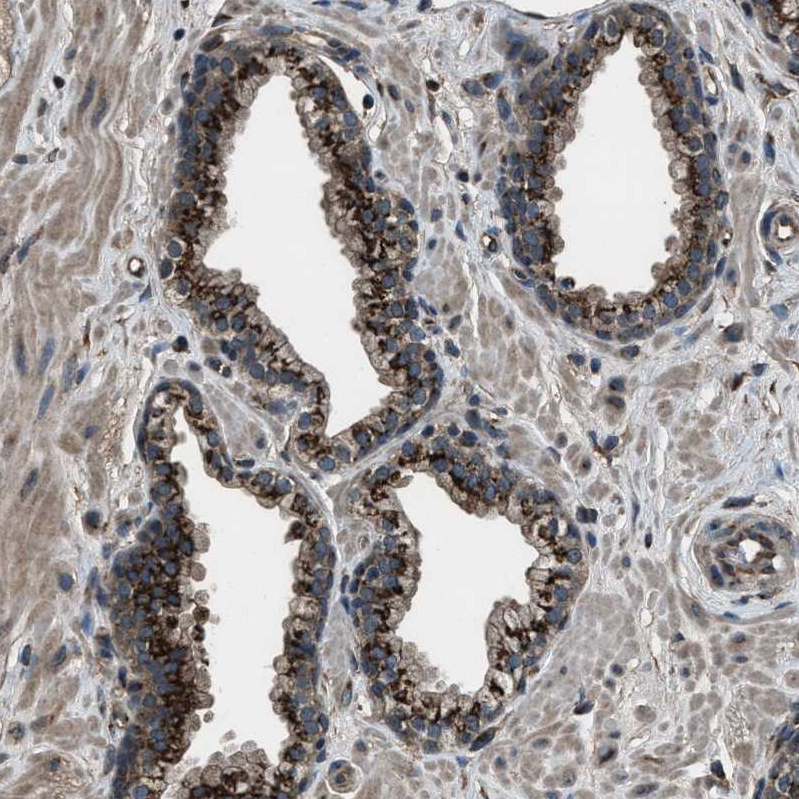

Immunohistochemical staining of human pancreas shows moderate granular cytoplasmic positivity in exocrine glandular cells.